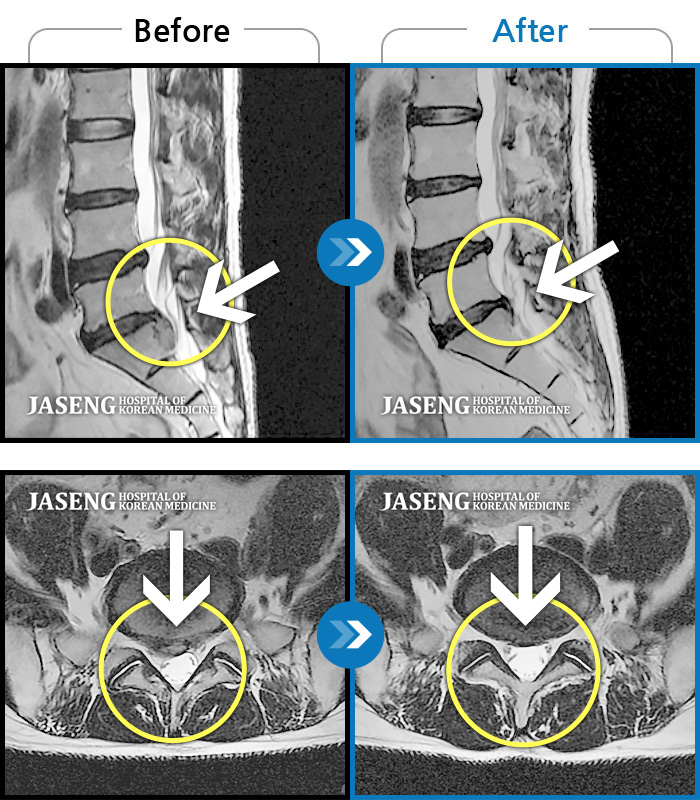

Before

After

환자에게 사전 동의를 받아 동일 조건에서 촬영되었습니다.

개인에 따라 치료 후 부작용이 발생할 수 있으니 의료진과 상담 후 치료를 진행하시기 바랍니다.

오른쪽 허리 골반 통증, 보행시 우측 다리까지 통증 및 당김 증상

좌측 엉덩이 통증 및 허벅지 당김 증상